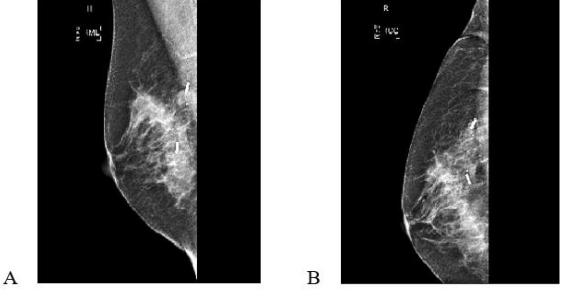

Directly after the procedure, cranio-caudal (CC) and medio-lateral (ML) mammograms were obtained to confirm accurate placement (Figure 1). Skin marking with a permanent pen was also done to indicate site and depth of lesion if the localization was performed on the day of surgery to aid the site of surgical excision. In most cases the localization was done to bracket the extreme ends of the lesion either medial and lateral or superior and inferior.

Figure 1: 51yr old with 31 BMI and BRA size 38 DD  with multifocal DCIS measuring  50mm on pre op imaging, post op specimen weighed 150gm, tumerectomy with partial breast reconstruction lateral intercostal artery perforator flap. Margins clear. Mediolateral (A) and Craniocaudal (B) mammograms showing two bracketing wires marking the medial and lateral extent of disease. Specimen X ray shows radiologically clear margins (C).